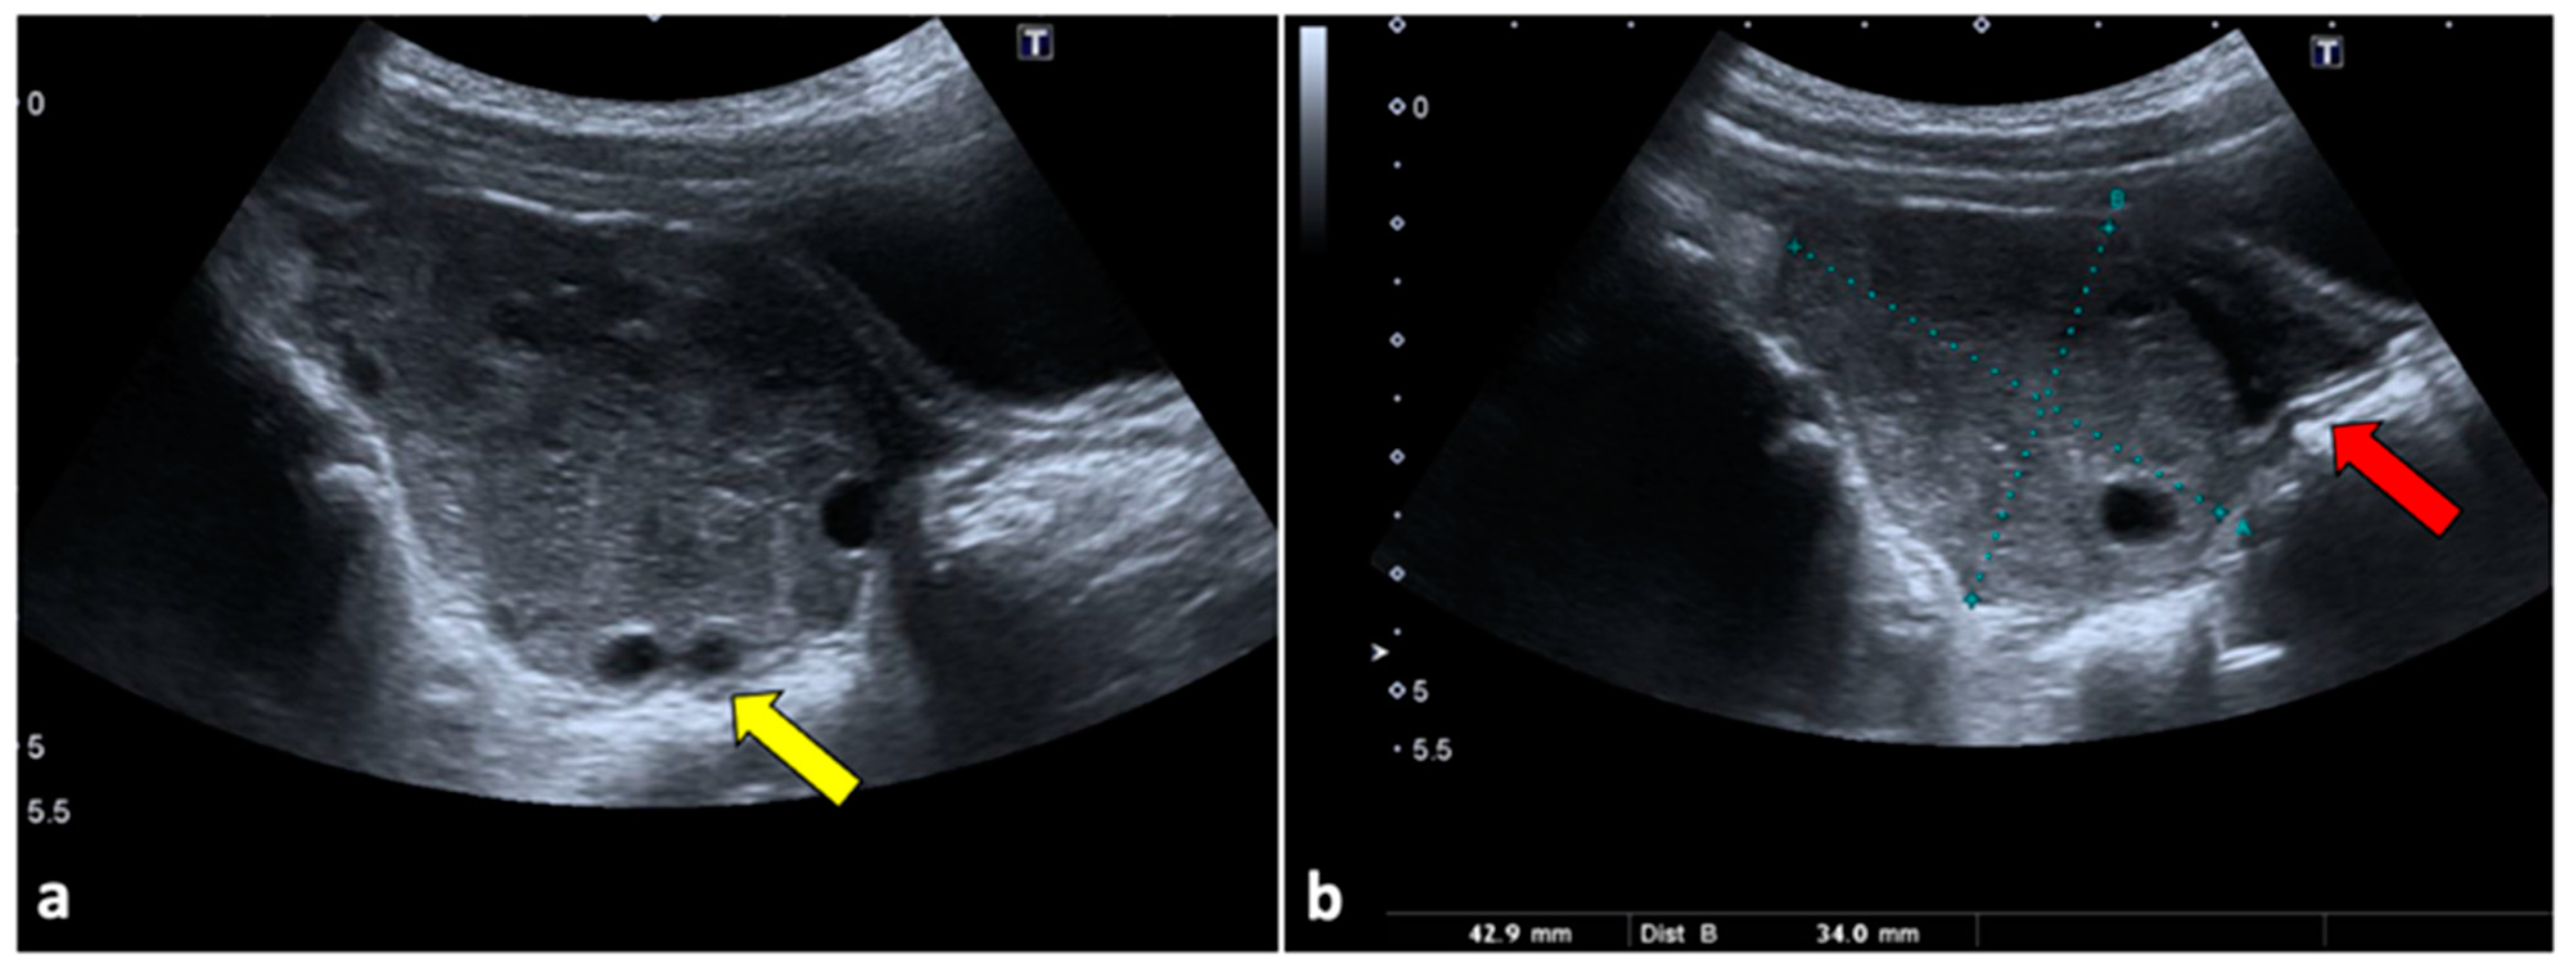

Figure 1.

Ovarian torsion in an eight-year-old patient presenting at the emergency department with aching right pelvic pain for a few hours. Transabdominal US examination (a,b) shows that the right ovary is grossly enlarged (long axis: 42.9 mm; short axis 34 mm) and abnormally located in the midline. The ovary appears slightly echogenic, with many small cysts at the periphery (yellow arrow). Small volume free fluid with tiny echoes is present in the pelvis (red arrow). During the Doppler US evaluation, no vascular flow was noticed (not shown).